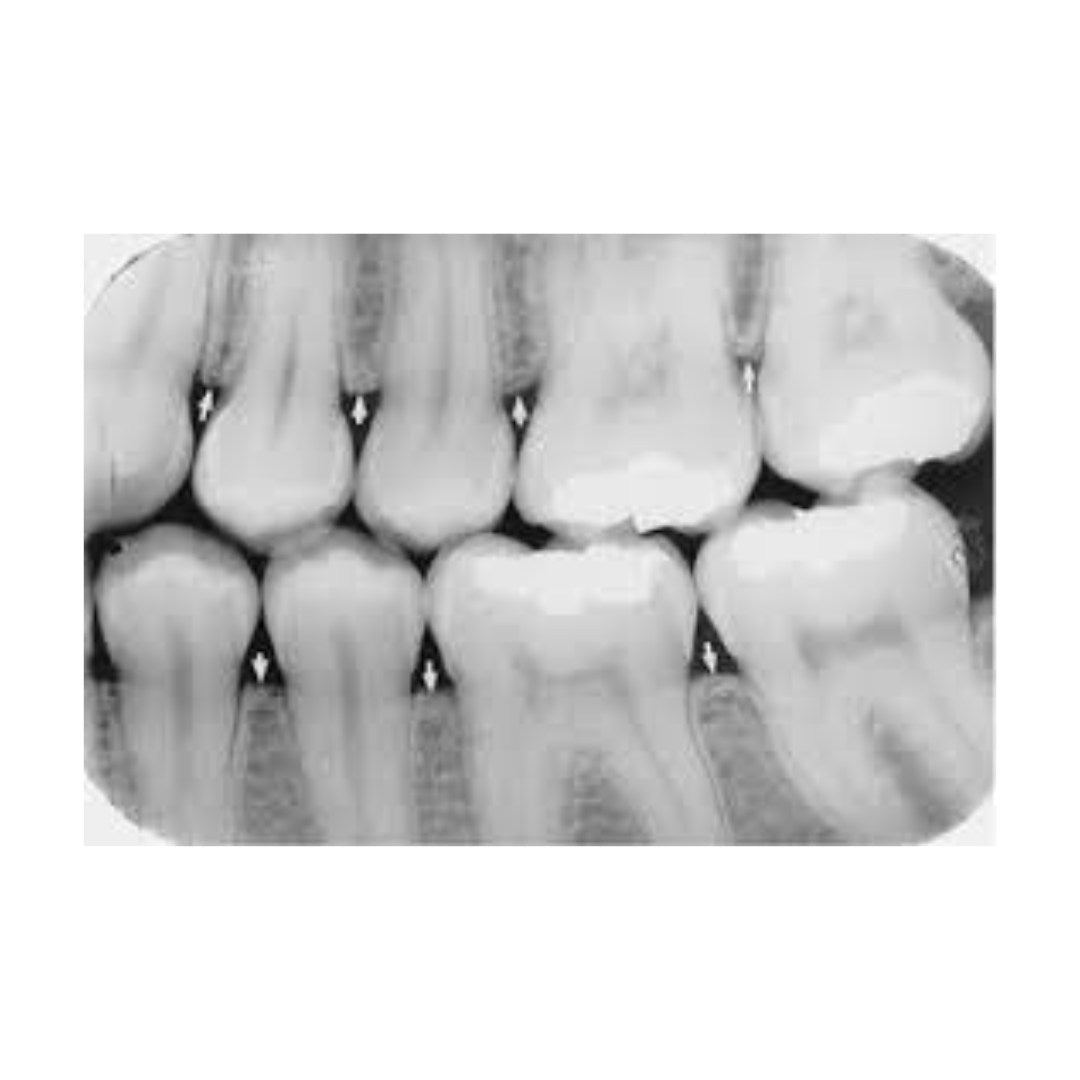

Røntgenbilder gir verdifulle innblikk i tannhelsen din. Ved å bruke røntgen kan tannlegen identifisere tidlige tegn på karies, tannråte, infeksjoner, betennelser og andre potensielle problemer som kan gå ubemerket hen. Det gjør det lettere å sette i gang tiltak tidlig, slik at små problemer ikke utvikler seg til store og kostbare behandlinger.

Røntgenbildene kan også brukes til å overvåke fremdriften i behandlinger som tannregulering, implantater eller rotfylling. Ved å ha tilgang til historiske røntgenbilder kan tannlegen vurdere endringer over tid, og tilpasse behandlingen etter behov.